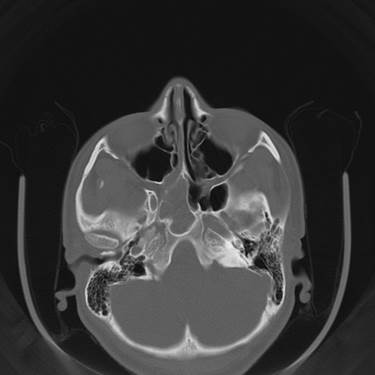

Полипозный этмоидит

Полипозный этмоидит 110 фото